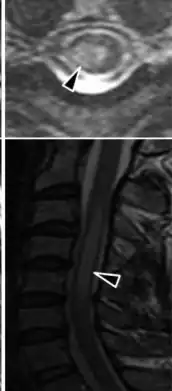

| MRI acute myelitis | |

Myelitis has an extensive differential diagnosis. The type of onset (acute versus subacute/chronic) along with associated symptoms such as the presence of pain, constitutional symptoms that encompass fever, malaise, weight loss or a cutaneous rash may help identify the cause of myelitis. In order to establish a diagnosis of myelitis, one has to localize the spinal cord level, and exclude cerebral and neuromuscular diseases. Also a detailed medical history, a careful neurologic examination, and imaging studies using magnetic resonance imaging (MRI) are needed. In respect to the cause of the process, further work-up would help identify the cause and guide treatment. Full spine MRI is warranted, especially with acute onset myelitis, to evaluate for structural lesions that may require surgical intervention, or disseminated disease.[11] Adding gadolinium further increases diagnostic sensitivity. A brain MRI may be needed to identify the extent of central nervous system (CNS) involvement. Lumbar puncture is important for the diagnosis of acute myelitis when a tumoral process, inflammatory or infectious cause are suspected, or the MRI is normal or non-specific. Complementary blood tests are also of value in establishing a firm diagnosis. Rarely, a biopsy of a mass lesion may become necessary when the cause is uncertain. However, in 15–30% of people with subacute or chronic myelitis, a clear cause is never uncovered.[9]